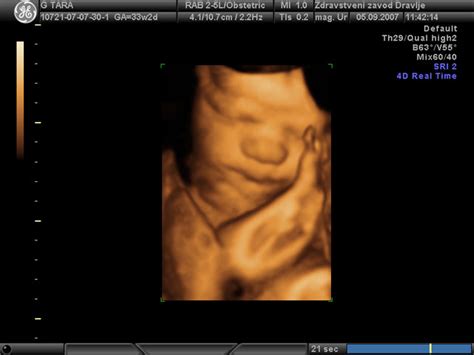

Poleg osnovnih genetskih testiranj obstajajo tudi druge preiskave, ki jih lahko nosečnica opravi na željo, vendar so samoplačniške. Sem spadajo dodatni ultrazvočni pregledi, kot je 3D/4D ultrazvok, ter zgodnja morfologija ploda in dvojni hormonski test.